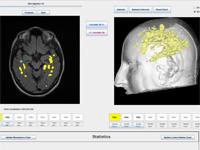

A Novel MRI Visualization Tool for White Matter Pathology in Multiple Sclerosis

We developed a tool to visualize MS lesions and their 3D surface models to show changes in the lesions over time. These can be shown as an animation to elucidate differences across scanning sessions. With this software, a volumetric sub-region can be selected from the 3D model for zooming or animation, and a point on the 3D model can be selected to highlight all lesions connected to it. The total volume of lesions can be calculated, displayed as a chart, and exported.

(poster, online abstract @ SfN, reference).

Concurrent Visualization of and Mapping between 2D and 3D Medical Images for Disease Pattern Analysis

We present a software tool to highlight and display regions of interest in 2D medical images and their 3D mesh model counterparts. This tool can help researchers visualize and compare brain lesions and tissues in 2D and 3D at the same time.

(conference article, online article @ VBL, reference).